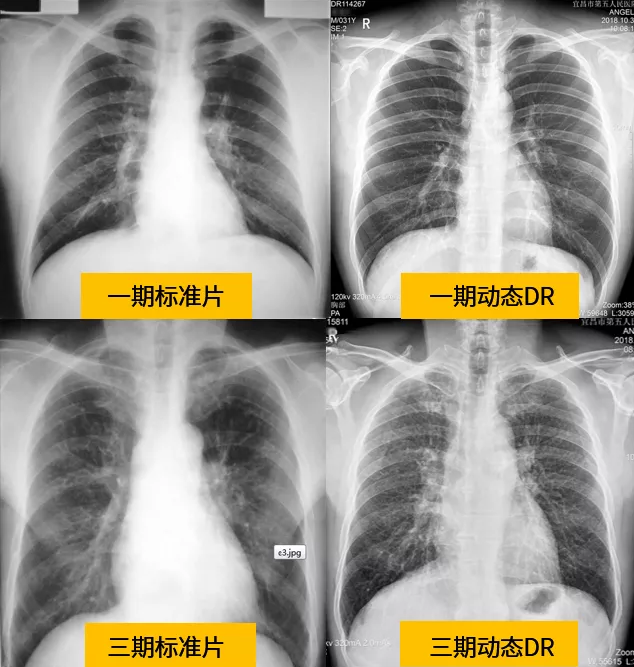

針對塵肺病在小陰影的特征和細(xì)節(jié)判斷上,傳統(tǒng)DR讀片誤差很難避免,也導(dǎo)致了對塵肺病期別的判斷誤差。由于各陰影間交叉重疊,不規(guī)則小陰影容易誤判為圓形小陰影。小陰影密集度完全靠讀片者憑工作經(jīng)驗(yàn)和比較標(biāo)準(zhǔn)片進(jìn)行判斷,而標(biāo)準(zhǔn)片只反映了密集度的某個截面,當(dāng)所讀片情況與標(biāo)準(zhǔn)片有差異時,則難以判斷。

動態(tài)平板DR屬于多功能診斷專用設(shè)備,具備全身數(shù)字化攝片,數(shù)字化透視,數(shù)字化造影(如T管造影圖),脊柱、四肢全長攝片(拼接圖),職業(yè)性塵肺體檢等功能,可做消化道造影檢查,作為數(shù)字胃腸機(jī)的較好備用補(bǔ)充。

與傳統(tǒng)DR設(shè)備不同,動態(tài)平板DR已不再局限于簡單的拍片功能,而是具有高清拍片、大幅面透視、高清點(diǎn)片、實(shí)時回放、自動曝光控制、全身拼接等多種功能。解決了傳統(tǒng)DR盲拍的劣勢,具有可視化操作功能,盡可能的避免誤診發(fā)生,極大的提高了診斷的準(zhǔn)確性。